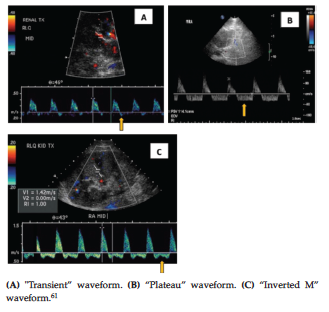

The reversed diastolic waveform was described (in the main or segmental renal arteries), when retrograde blood flow occurred at any time point during the diastole, regardless of whether antegrade flow has happened. There are 3 typical shapes of reversed diastolic waveforms: type 1 or “transient” waveform (Figure 3A), in which the reversed diastolic waveform returns to baseline before end diastole; type 2 or “plateau” waveform (Figure 3B), in which a flat reversed flow remains relatively constant throughout diastole; and type 3 or “inverted M” waveform (Figure 3C), in which reversed flow throughout diastole has middiastolic deceleration.39

Previous studies have described a plateaulike or inverted M waveform associated with TRVT, whereas reversal of flow that is limited to the early diastole has been seen with severe rejection or acute tubular necrosis of the graft.47 However, this observation was not confirmed by Lockhart and associates,39 who showed that all 3 waveform types could be present in TRVT patients, and reversed diastolic waveform types were not specific for any cause. The entire diastole flow waveforms (plateau-like and inverted M shapes) represent higher vascular resistance and are associated with a higher rate of graft loss than transient waveform morphologies.37,39,48,49